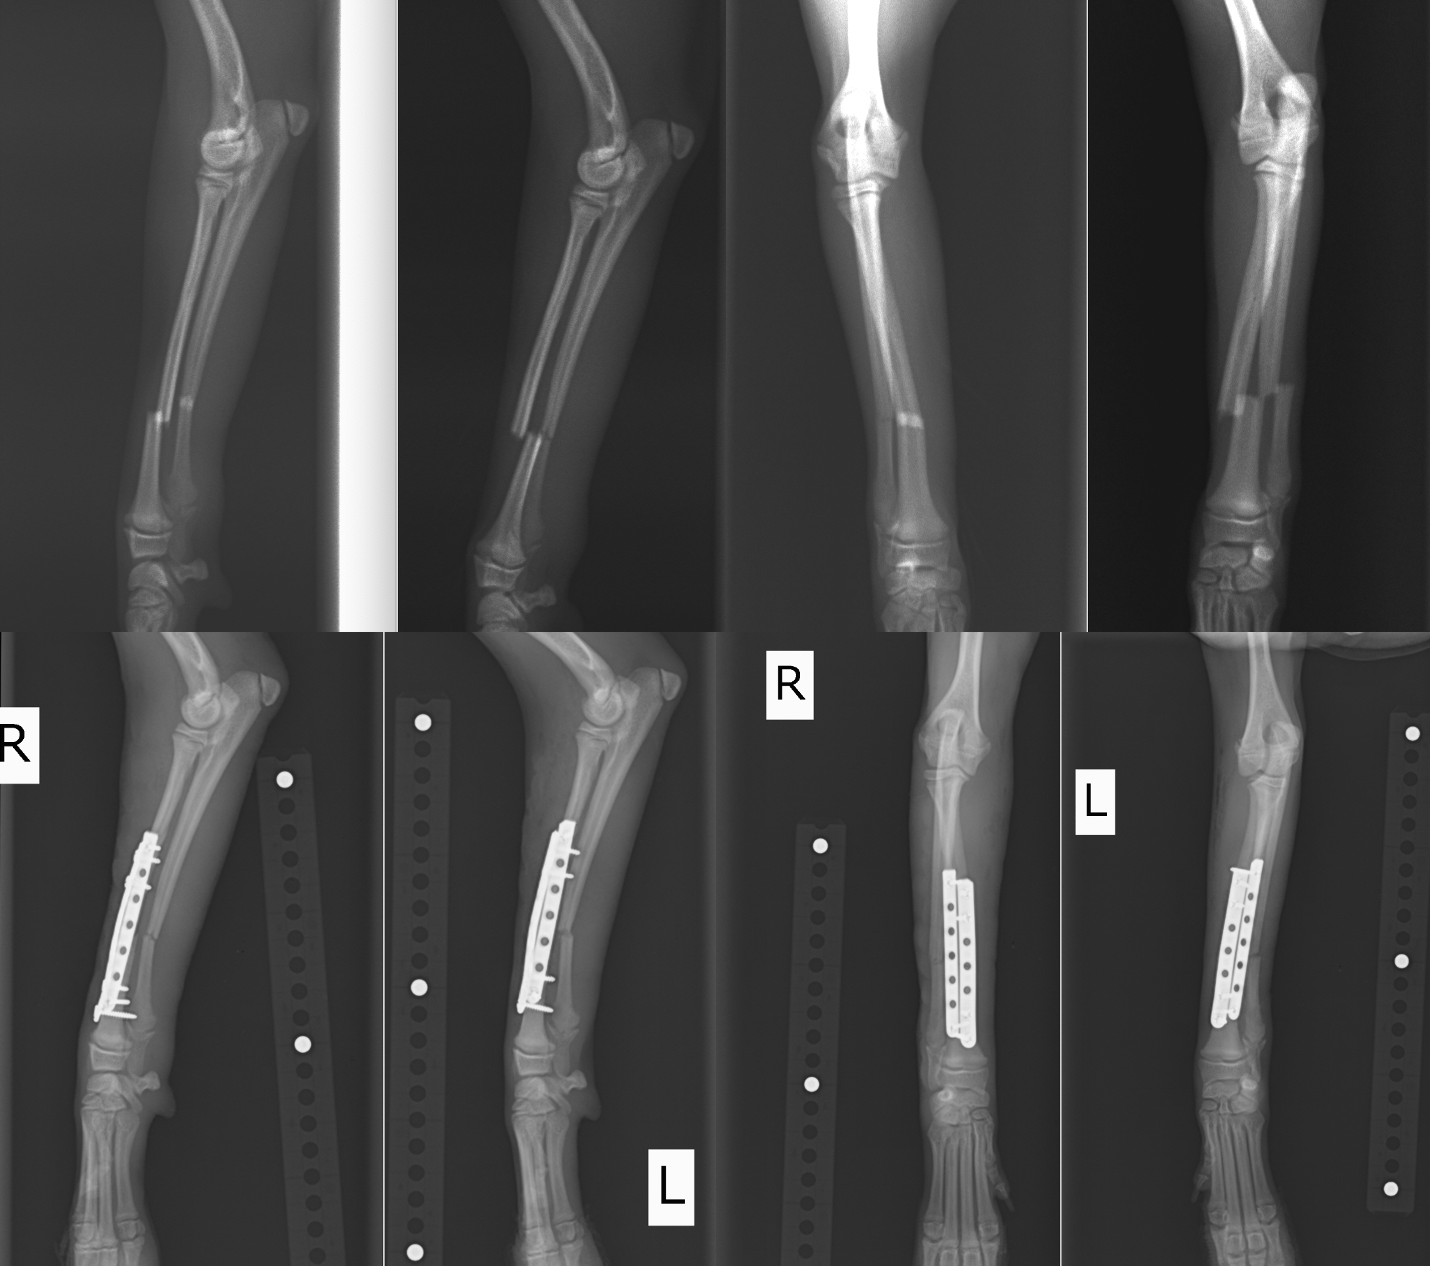

近年、小型犬が増加しているのに比例して橈尺骨骨折が増加しています。橈尺骨骨折にはプレートを2枚入れる方法を用います。2枚入れることで強度を増すことができプレートの破綻を防止できます。また、1枚ずつプレート抜去が可能であるため、ある程度骨が固まってきたら1枚抜去し、さらに骨化を促進し、もう一枚抜去するという方法が可能です。そうすることで癒合不全(骨化が遅れること)を防止し、プレート抜去後の再骨折のリスクを減らすことができます。

イタリアングレーハウンドの橈尺骨骨折です。2.0mmスクリューを使用しています。

トイプードル9歳の橈尺骨骨折です。1.5mmスクリューを使用しています。

トイプードル2歳の橈尺骨骨折です。1.5mmスクリューを使用しています。 上の3症例ともにやや中央寄りの先端部の橈尺骨の横骨折(遠位骨幹部橈尺骨横骨折)です。直線のプレートを使用しています。

ポメラニアン半年齢の橈骨尺骨骨折です。1.3mmの超小型スクリューを使用しました。 上の4症例はやや中央寄りの先端部の橈尺骨の横骨折(遠位骨幹部橈尺骨横骨折)です。直線のプレートを使用しています。

前足を両方とも同時に骨折してしまったポメラニアン。まだ4ヶ月で体重も2kgに満たない子犬でした。1.3mmと1.1mmのプレートスクリューを用いて整復しています。

両側同時に骨折してしまったトイプードル。かなり遠位ぎりぎりで折れているのでT字プレートを使用しています。